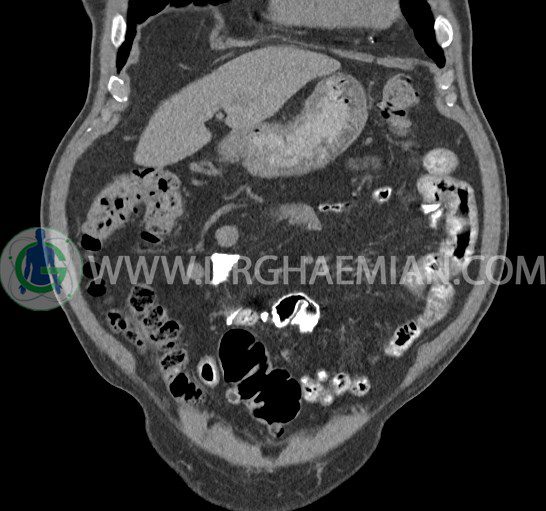

سی تی اسکن لگن یکی از روش های تصویربرداری با سی تی اسکن است. این روش با استفاده از تشعشعات تصاویر عرضی از ناحیه شکمی ایجاد میکند. در این کیس ديورتيكولوزيس، کیست های کورتیکال در هر دو کلیه، لنفادنوپاتی، کلسیفیکاسیون دیواره آئورت و شریان ایلیاک، تغییرات DJD ناحیه توراکولومبار و پروستات بزرگتر از عادی دیده می شود.

در سي تي اسکن اسپيرال شکم و لگن با و بدون کنتراست خوراکی و وريدی (مولتي ديدکتور 16 با مقاطع ظريف و بازسازي هاي ساژيتال و کرونال):

– کيست هاي کورتيکال ساده به قطر 5 mm تا 50 mm در کليه راست و به قطر 5mm تا 55 mm در کليه چپ

– توده ايزودنس به ابعاد mm 17 x 28 در پره ائورت مجاور قسمت تحتاني D3 دئودنوم مطرح کننده لنفادنوپاتي و با احتمال کمتر آنوريسم ترومبوزه (نيازمند مطابقت سونولوژيک)

– ديورتيكولوزيس در کولون نزولي وسيگموئيد

لنفادنوپاتي به ابعاد mm 22 x 25 مجاور شريان ايلياک خارجي چپ و به ابعاد mm 17 x 28 مجاور شريان ايلياک خارجي راست

– تغييرات DJD در ناحيه توراکولومبار و